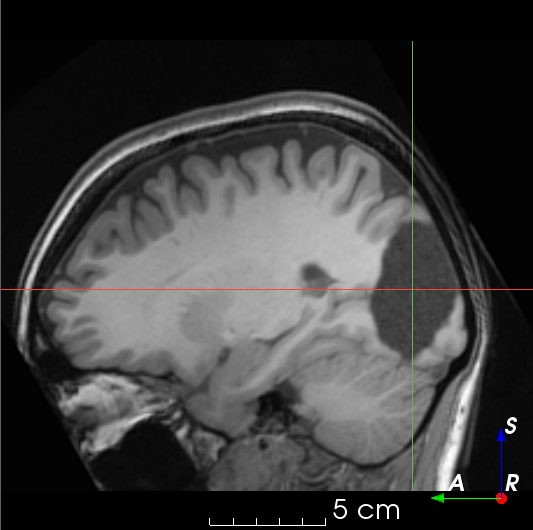

(f)

Figure 3: Manual labels from Rater A (green) and Rater D, the model trained with PubFull + EpiPre + Pseudo (magenta). Errors caused by a (a) small resection, (b) blood clot in cavity and (c) brain shift; segmentations corresponding to the (d) 50th, (e) 75th and (f) 100th percentiles giving a DSC of 81.7, 86.5 and 93.8, respectively.

We trained a model using PubFull, EpiPre and Pseudo (2371 images), obtaining a DSC of 81.7 (14.2). Adding the pseudo-labels to PubFull and EpiPre did not significantly improve performance (p=0.176𝑝0.176p=0.176), indicating our semi-supervised learning approach provided no advantage. Predictions from this model are shown in Fig. 3.

Predictions errors are mostly due to 1) resection of size comparable to sulci (Fig. 6a), 2) unanticipated intensities, such as those caused by the presence of blood clots in the cavity (Fig. 6b), 3) brain shift (Fig. 6c) and 4) white matter hypointensities (Fig. 6e). Further work will involve using different internal and external cavity textures, carefully sampling the resection volume, simulating brain shift using biomechanical models, and quantifying epistemic and aleatoric segmentation uncertainty to better assess model performance [24].